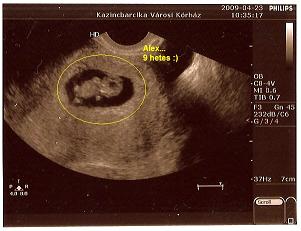

Edinka

én is gratulálok neked és még emlékszem a 2008 as hozzászólásaidra, és a sok várakozásra, csalódásra. nagyon örülök, hogy végre lesz tesó.

Hmeme

neked is szívből gratulálok.